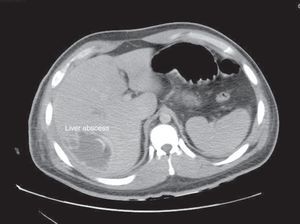

Its usual presentation includes fever, weight loss, and abdominal pain. PA is commonly polymicrobial. However, Klebsiella pneumoniae, Escherichia coli are often predominant.3 Diagnosis is performed with imaging studies, such as ultrasound (US) or a CT scan. Injuries are usually located in the right lobe of the liver.4 In the case of AA, it is confirmed with blood tests. Alkaline phosphatase usually increases in 90% of PA cases.

Regarding the imaging studies performed, US and CT scans were conducted in 44 patients, only US on 54 patients, and only TAC on 32 patients (Figure 1). Abscesses were located on the right side in 84 (56%) patients, on the left side in 40 (26%), and on both sides in 26 (17.3%). The number of reported abscesses was 1.27±1.04. There was 1 abscess reported in 108 (72%) patients, 2 in 20 (13.3%), and 3 or more in 18 (12%). Average size was 3.96cm±4.7; the largest reported size was 18cm. There were 8 (5.4%) reported with a thickened abscess wall, 26 (17.3%) with edge highlighting, 8 (5.4%) with pneumobilia, and 4 with gas present (2.6%). Subcapsular rupture occurred in 22 (14.6%) patients. There were 2 cases of portal thrombophlebitis reported.